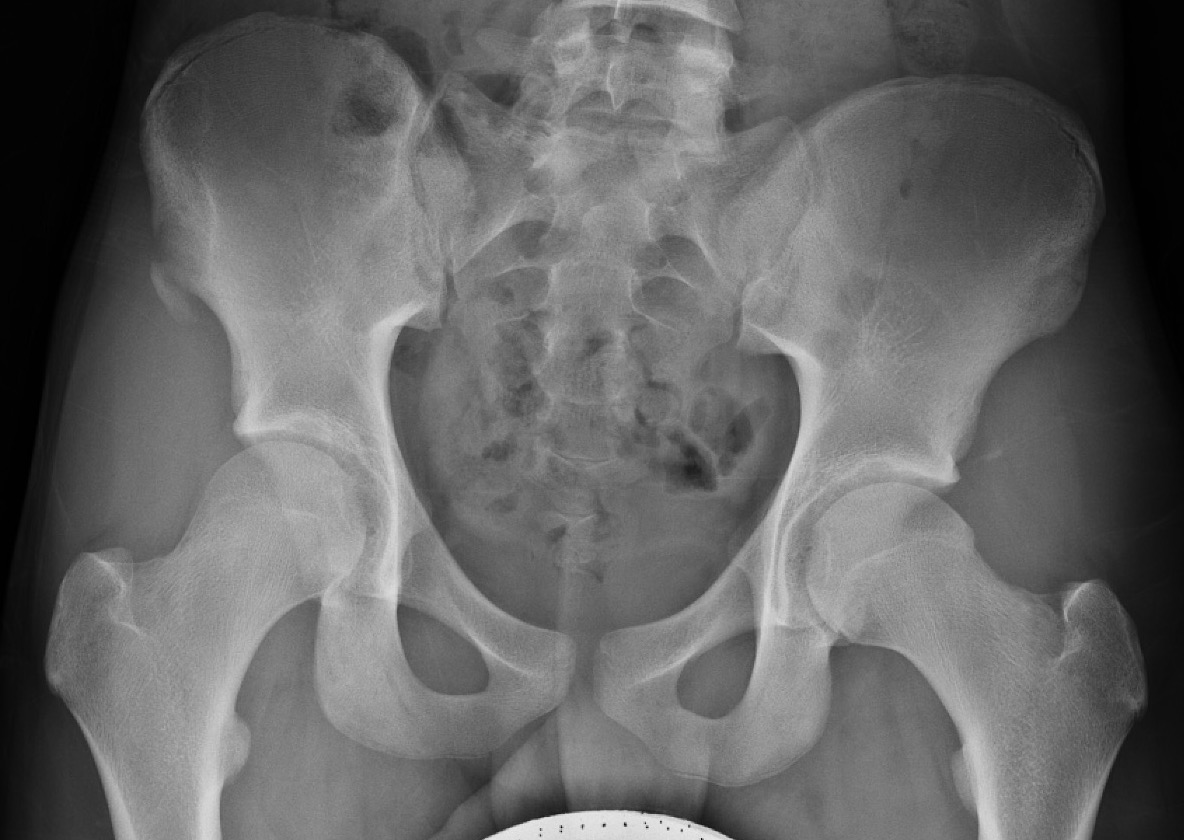

ASIS Avulsion

Attachments

Sartorius & Tensor fascia lata

Imaging

ASIS displaced 1ASIS displaced 2